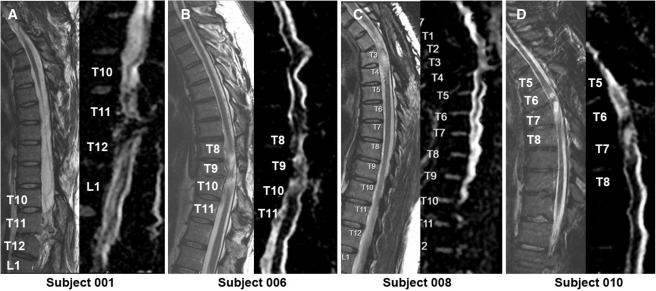

本次發(fā)布的I期臨床研究旨在評估神經(jīng)干細胞移植治療慢性胸椎脊髓損傷的安全性和初步療效。研究選取了四名完全性ASIA-A級胸部SCI患者作為受試者,這些患者的損傷時間均超過一年,且在接受任何其他形式的有效治療后仍未見明顯好轉(zhuǎn)。

每位受試者接受了每個注射點含有2×105個神經(jīng)干細胞,通過定制的立體定向設備,雙側(cè)注入損傷部位周圍的剩余組織及下方約一個節(jié)段的內(nèi)側(cè)白質(zhì)區(qū),整個過程由術(shù)中熒光透視成像指導完成。

臨床結(jié)果:

1.神經(jīng)系統(tǒng)反應概覽:按ISNCSCI隨訪,2名受試者(001、010)在移植后出現(xiàn)了明顯的神經(jīng)學改善:001在移植后2年曾上升兩個節(jié)段,5年回落至上升1個節(jié)段;010則在整個5年隨訪期間保持了穩(wěn)定的神經(jīng)功能提升。

2.免疫抑制與免疫反應:四名受試者均在移植后12周停用他克莫司和霉酚酸酯;雖有一例(010)在6個月檢測到陽性抗HLA抗體,但并非針對供體特異性抗體,研究組認為這并非由NSC移植直接引起的免疫排斥反應。

3.疼痛與生活質(zhì)量:疼痛方面,001和006報告總體疼痛下降,008疼痛加重且因骶骨潰瘍在30個月時發(fā)生嚴重不良事件導致生活自理能力(SCIM)明顯下降,010的疼痛和SCIM變化較小,總體3名患者SCIM未見顯著改善。

4.影像學評估:術(shù)后MRI顯示所有患者存在不同程度的局灶性脊髓軟化,但未見新的并發(fā)影像學征象(如水腫、增強或積液);DTI提示脊髓束外觀穩(wěn)定,未見廣泛重塑或纖維束改善。

5.神經(jīng)生理反應:電生理檢查顯示多名患者在移植后數(shù)月至數(shù)年間出現(xiàn)新的肌電活動與對強化動作的反應(例如001、006、010在不同節(jié)段出現(xiàn)新發(fā)EMG信號和增強的肌肉反應),提示部分節(jié)段出現(xiàn)了功能性神經(jīng)肌肉恢復跡象。

研究結(jié)果表明,神經(jīng)干細胞移植是一種可行且相對安全的方法,能夠在一定程度上促進慢性胸椎SCI患者的神經(jīng)功能恢復。